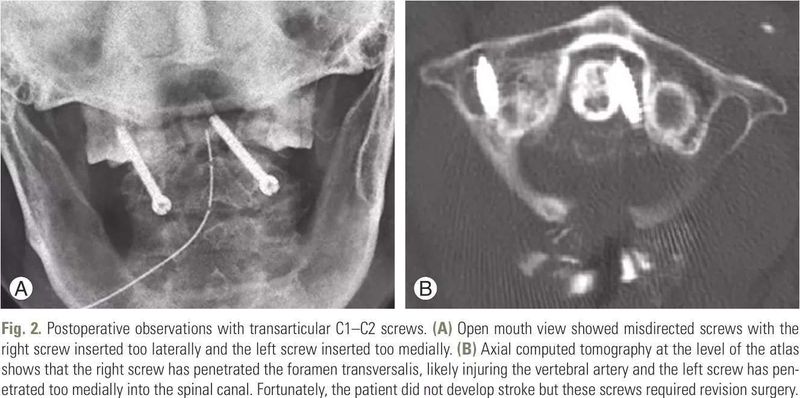

醫(yī)生面對(duì)頸椎手術(shù)并發(fā)癥,陜西方言“很木亂”,文藝點(diǎn)說“為伊消得人憔悴”,了解并發(fā)癥的發(fā)生概率、對(duì)策以及發(fā)生并發(fā)癥的可能原因和未來轉(zhuǎn)歸,防患于未然。這期,探討一下頸椎后路手術(shù)并發(fā)癥問題。 1頸椎后路手術(shù)并發(fā)癥有哪些? 如何預(yù)防和降低? 刊載在2016年《Asian Spine Journal》的一篇題為“Complications of Anterior and Posterior Cervical Spine Surgery”(頸椎前路和后路手術(shù)的并發(fā)癥)的文獻(xiàn)中也詳細(xì)講解了頸椎后路的并發(fā)癥,我們一起來看看。 頸椎后路手術(shù)并發(fā)癥 01脊髓和神經(jīng)根損傷 據(jù)報(bào)道,神經(jīng)系統(tǒng)并發(fā)癥的總發(fā)生率為0.18%,如果曾經(jīng)接受過嚴(yán)重頸椎后凸畸形矯正,發(fā)生率將會(huì)增加(2.6%)。后路矯正手術(shù)治療頸椎后凸畸形時(shí),晚期神經(jīng)系統(tǒng)并發(fā)癥可通過以下措施避免:椎間孔狹窄和各脊髓節(jié)段不超過9.7°的后凸畸形矯正行預(yù)防性椎間孔成形術(shù),避免于C4-C5段行后凸矯正,因此節(jié)段發(fā)生最大脊髓后移時(shí)易導(dǎo)致C5神經(jīng)根麻痹。此問題較為常見,但多數(shù)情況下,可自愈。與前路手術(shù)相似,脊髓神經(jīng)監(jiān)測儀是一種較好的輔助監(jiān)測工具。 02螺釘固定 寰椎處螺釘錯(cuò)位的發(fā)生率為0%-4%,樞椎為0%-7%。C1-C2經(jīng)關(guān)節(jié)螺釘或Magerl螺釘也會(huì)造成椎動(dòng)脈損傷、神經(jīng)功能障礙或骨缺損(下圖)。椎動(dòng)脈損傷是螺釘固定最危險(xiǎn)的并發(fā)癥之一,引起該并發(fā)癥的原因通常是頸椎椎弓根螺釘嵌入不正確導(dǎo)致椎動(dòng)脈損傷。醫(yī)源性椎動(dòng)脈損傷的發(fā)生率為1.3%,其中4%發(fā)生于Magerl螺釘內(nèi)固定。幸運(yùn)的是,神經(jīng)功能障礙風(fēng)險(xiǎn)較低(0.2%)。如果兩側(cè)椎動(dòng)脈均受損,死亡率將大大增加。螺釘偏向外側(cè)常會(huì)引起橫孔穿透,導(dǎo)致椎動(dòng)脈損傷。目前傾向于應(yīng)用術(shù)中CT和計(jì)算機(jī)輔助導(dǎo)航系統(tǒng)技術(shù)改善螺釘方向并減少螺旋穿孔。 術(shù)后片頸C1-C2經(jīng)關(guān)節(jié)間螺釘固定 圖A:開口位片可見錯(cuò)位螺釘,其中右側(cè)螺釘過度偏向外側(cè),左螺釘過度偏向內(nèi)側(cè)插入。 圖B:寰椎軸向CT掃描表明,右側(cè)螺釘穿透橫孔,可能傷及椎動(dòng)脈,左側(cè)螺釘過度向內(nèi)側(cè)嵌入以致穿入椎管。幸運(yùn)的是,患者并沒有發(fā)展為偏癱,但這些螺釘需行翻修手術(shù)。 下頸椎側(cè)塊螺釘是神經(jīng)根損傷(1.3%)和側(cè)塊骨折的風(fēng)險(xiǎn)因素。X線透視監(jiān)控可以預(yù)防插入側(cè)塊螺釘時(shí)對(duì)神經(jīng)根造成的直接損傷。插入時(shí)矢狀角若小于15°,則可能導(dǎo)致突出螺釘對(duì)神經(jīng)根的刺激(下圖)。軸向軌跡與中線比偏向外側(cè)30°,可能誘發(fā)側(cè)塊骨折(1.6%)或螺釘切割脫出(1.3%)。但是,神經(jīng)受損并不常見。螺釘過度向內(nèi)側(cè)放置可致椎動(dòng)脈損傷。 術(shù)后(A)側(cè)位計(jì)算機(jī)斷層(CT)掃描和(B)三維CT重建顯示側(cè)塊螺釘穿透至神經(jīng)根孔(箭頭)。因患者無癥狀,保留這些螺釘于原位。 03后路枕頸部固定 枕頸固定術(shù)中,枕骨螺釘?shù)木珳?zhǔn)插入是預(yù)防并發(fā)癥的關(guān)鍵。螺釘向頭側(cè)插入至上項(xiàng)線時(shí)會(huì)損傷橫竇。據(jù)記錄,4.2%-7%的病例出現(xiàn)螺釘松動(dòng),嵌入螺釘?shù)倪^程中有0%-4.2%的病例出現(xiàn)硬腦膜撕裂。該區(qū)域頭皮較薄,植入物凸出可導(dǎo)致皮膚糜爛。硬腦膜撕裂可以發(fā)生于枕骨鉆孔以固定的鋼絲刺穿(25%-28%)。硬腦膜撕裂會(huì)導(dǎo)致腦脊液漏,但螺釘插入到鉆孔通常能夠阻止腦脊液漏。枕頸部融合術(shù)晚期并發(fā)癥包括假關(guān)節(jié)(6%)和鄰近椎體退變(7%)。 04C5麻痹 Yonenobu等人報(bào)道,術(shù)后早期C5神經(jīng)根癥狀惡化發(fā)生率為3.4%。這些損傷通常以運(yùn)動(dòng)性為主,但也可能出現(xiàn)感覺和神經(jīng)根性疼痛。術(shù)后20天內(nèi)都可能會(huì)出現(xiàn)C5功能障礙,通??苫謴?fù),但時(shí)間需要幾個(gè)星期、幾個(gè)月或長達(dá)6年??赡懿∫蚴菧p壓的脊髓后移引起牽引對(duì)神經(jīng)根造成損傷。C5位于頸椎前凸的頂點(diǎn),神經(jīng)根在椎管內(nèi)走行短且直,容易受損。脊髓向后偏移會(huì)引發(fā)C5神經(jīng)根拴系效應(yīng),并可能超出其承受極限。三角肌由C5神經(jīng)根進(jìn)行單一支配,因此任何神經(jīng)功能障礙對(duì)患者機(jī)能都會(huì)產(chǎn)生深遠(yuǎn)影響。早先存在三角肌無力、椎間孔狹窄、后縱韌帶骨化和行椎板切除固定術(shù)的患者應(yīng)考慮預(yù)防性椎間孔成形術(shù)。 05椎管成形后“再關(guān)門” 據(jù)報(bào)道,椎板成形術(shù)后“再關(guān)門”(下圖)的發(fā)生率為40%。而該并發(fā)癥僅被報(bào)道發(fā)生于縫合固定術(shù),尚未在螺釘或鋼板固定術(shù)中被觀察到。Lee等人發(fā)現(xiàn)術(shù)后6個(gè)月,行Hirabayashi單開門椎板成形術(shù)的患者前后徑增大,開角(兩側(cè)關(guān)節(jié)突內(nèi)側(cè)端連線和開口椎板兩側(cè)端連線夾角)約減小10%。對(duì)于雙開門椎板成形術(shù),椎板之間脊髓術(shù)后移位可能導(dǎo)致脊髓病惡化。 軸位CT顯示(A)椎板成形術(shù)后鉸鏈骨折和(B)“再關(guān)門”,應(yīng)施行椎板切除翻修手術(shù)和融合術(shù)。 06椎板切除術(shù)后脊柱后凸畸形 多節(jié)段椎板切除術(shù)后脊柱后凸畸形的發(fā)生率為20%(下圖)。老年患者頸椎可能部分融合,更穩(wěn)定。因此,術(shù)后后凸畸形在年輕患者中更為常見。椎板切除術(shù)是包括對(duì)影響后側(cè)穩(wěn)定的棘突、棘間和棘上韌帶、椎板、黃韌帶和受損囊變關(guān)節(jié)突的切除。正常屈伸持續(xù)施壓會(huì)導(dǎo)致后凸畸形。后凸畸形是逐漸形成的,因此患者在術(shù)后早期階段通常表現(xiàn)良好。頸部伸肌會(huì)出現(xiàn)持續(xù)性收縮,引起肌肉疲勞和頸部疼痛。兒童進(jìn)行性后凸畸形因軟骨終板生長產(chǎn)生壓力導(dǎo)致前側(cè)椎體楔狀變形。椎板切除術(shù)后脊柱后凸畸形常見的問題是矢狀面失平衡和軸向頸痛,少數(shù)出現(xiàn)神經(jīng)功能障礙。術(shù)后早期,牽引通??墒诡i部恢復(fù)對(duì)齊。椎板切除術(shù)忌用于無頸椎前凸的年輕患者。術(shù)中不應(yīng)破壞后側(cè)關(guān)節(jié)突。對(duì)于這些患者,同時(shí)應(yīng)考慮實(shí)行融合術(shù)。 C2-4椎板切除術(shù)后脊柱后凸畸形患者的側(cè)位X線片。需施行后路固定翻修手術(shù)和融合術(shù)。 07微創(chuàng)手術(shù) 微創(chuàng)手術(shù)的優(yōu)勢為肌肉牽引、失血和術(shù)后疼痛的減少,盡管如此,該技術(shù)在頸椎治療中尚未得到廣泛認(rèn)可。微創(chuàng)手術(shù)可視范圍有限,可能導(dǎo)致更為嚴(yán)重的并發(fā)癥。于緊密的神經(jīng)孔處操作可能會(huì)損傷神經(jīng)根。直接脊髓損傷也可能發(fā)生于擴(kuò)張或減壓手術(shù)。手術(shù)中,建議采用透視成像技術(shù)小心地將鈍性擴(kuò)張器插入,應(yīng)防止其插入椎板間引起神經(jīng)損傷。據(jù)報(bào)道,微創(chuàng)減壓手術(shù)中硬腦膜撕裂的發(fā)生率為1.6%-6.6%。硬脊膜損傷時(shí),難以采用小型tubular牽開器接近和暴露,修復(fù)較困難,通常需改行開放手術(shù)。 2常見頸椎后路手術(shù)方式 (椎板成形與減壓融合)的并發(fā)癥有哪些? 椎板成形術(shù)并發(fā)癥 根據(jù)發(fā)表在《Journal of the American Academy of Orthopaedic Surgeons》的一篇名為“Cervical Laminoplasty:Indications,Surgical Considerations, and Clinical Outcomes ”(頸椎椎體成形術(shù)的適應(yīng)癥、手術(shù)注意事項(xiàng)和臨床結(jié)果)的文獻(xiàn),文中詳述了頸椎椎板成形術(shù)的常見并發(fā)癥,C5脊神經(jīng)麻痹、軸性頸痛、頸椎關(guān)節(jié)活動(dòng)度喪失和頸椎生理前曲消失等。 01C5脊神經(jīng)麻痹 椎板成形術(shù)后C5脊神經(jīng)麻痹的發(fā)生率在文獻(xiàn)中已有普遍報(bào)道。在一項(xiàng)對(duì)384例接受過前路椎間融合術(shù),次全切除術(shù),椎板切除術(shù)或椎板成形術(shù)治療的脊髓型頸椎病患者的研究中,Yonenobu等人報(bào)告稱總神經(jīng)系統(tǒng)并發(fā)癥發(fā)生率為5.5%。 02軸性頸痛 目前尚無報(bào)道椎板成形術(shù)可以減輕肩胛周圍和斜方肌區(qū)域的軸頸痛。其原因可能是由于小關(guān)節(jié)破壞或肌肉剝離。Hosono等人對(duì)26例行前路椎間融合術(shù)的患者和72例行椎板成形術(shù)的患者進(jìn)行了研究,發(fā)現(xiàn)行椎板成形術(shù)的患者頸部疼痛的發(fā)生率明顯高于行前路融合術(shù)的患者(分別為60%和19%)。接受椎板成形術(shù)的患者中有26%發(fā)生了術(shù)后軸性頸痛,術(shù)后平均持續(xù)5.5個(gè)月,并且在術(shù)后1至1.5年內(nèi)減輕。這些患者在術(shù)后2到3個(gè)月接受剛性頸托治療。 03頸椎關(guān)節(jié)活動(dòng)度喪失 盡管椎板成形術(shù)是保留頸椎活動(dòng)的手術(shù),但關(guān)節(jié)活動(dòng)度也可能會(huì)大大喪失。關(guān)節(jié)活動(dòng)度喪失可能歸因于相鄰椎板間骨性融合,后頸伸肌的破壞和/或手術(shù)后頸托的長期使用。行椎板成形術(shù)的患者中有28%至88%發(fā)生椎板間骨性融合,最常見于C2-C3。一些研究推測,這種情況可能是由于椎板成形術(shù)后開放的C3椎板變得更接近C2的棘突。 04頸椎生理曲度消失 在暴露側(cè)塊時(shí),外科醫(yī)生應(yīng)小心操作,否則可能會(huì)導(dǎo)致小關(guān)節(jié)囊破裂,導(dǎo)致加速脊椎疾病,軸向頸痛和脊柱前凸的喪失。一項(xiàng)對(duì)85位從C3到C7做過椎板成形術(shù)患者的研究中,Suk等人報(bào)告說關(guān)節(jié)活動(dòng)度喪失的患者占30%,大約喪失5°的頸椎生理曲度。椎板成形術(shù)后患者發(fā)生后凸畸形在10.6%。作者認(rèn)為影響脊柱后凸的術(shù)前因素是前凸角小余10°,屈曲時(shí)的后凸角大于伸展時(shí)的后凸角。 頸椎后路減壓融合術(shù)并發(fā)癥 發(fā)表在2020年6月《J Spine Surg》的一篇名為“Complications following posterior cervical decompression and fusion: a review of incidence, risk factors, and prevention strategies ”(回顧頸椎后路減壓融合術(shù)后的并發(fā)癥的發(fā)生率、危險(xiǎn)因素和預(yù)防策略)的文獻(xiàn),文中講述了頸椎后路減壓融合術(shù)的并發(fā)癥等相關(guān)內(nèi)容。 摘要:頸椎后路減壓融合術(shù)(PCF)是常見的治療各種頸椎病的外科手術(shù)技術(shù)。但是,與PCF相關(guān)的各種并發(fā)癥可能會(huì)對(duì)患者的預(yù)后產(chǎn)生負(fù)面影響。我們使用PubMed,Cochrane系統(tǒng)評(píng)價(jià)數(shù)據(jù)庫和Google學(xué)術(shù)搜索對(duì)PCF術(shù)后最常見的并發(fā)癥進(jìn)行了全面的文獻(xiàn)綜述。在當(dāng)前文獻(xiàn)中,PCF的總并發(fā)癥發(fā)生率估計(jì)為約15%至25%。最常見的早期并發(fā)癥包括急性失血性貧血,手術(shù)傷口感染(SSI),C5脊神經(jīng)麻痹和硬膜撕裂;最常見的長期并發(fā)癥包括鄰近節(jié)段退變,交界性后凸和假性關(guān)節(jié)形成。認(rèn)為三種主要機(jī)制可導(dǎo)致并發(fā)癥。首先,更高水平的融合,肥胖和更復(fù)雜的病理可能會(huì)增加計(jì)劃手術(shù)的侵入性,從而增加并發(fā)癥。其次,由于各種患者因素(例如吸煙,糖尿病,體弱多病,使用類固醇和其他合并癥)導(dǎo)致血液流動(dòng)不良,可能會(huì)損害傷口的愈合和關(guān)節(jié)固定術(shù)。最后,近端融合椎(UIV)和遠(yuǎn)端融合椎(LIV)增加的生物力學(xué)應(yīng)力可能使患者容易發(fā)生慢性退變,并導(dǎo)致鄰近水平的退變和/或連接問題。術(shù)前減少可改變的危險(xiǎn)因素能降低總體并發(fā)癥的發(fā)生率。術(shù)中適當(dāng)減壓可以減少神經(jīng)系統(tǒng)損傷。通過細(xì)致的傷口閉合可以減少手術(shù)傷口感染,從而最大程度地減少死隙,引流管的放置、傷口內(nèi)使用抗生素。仔細(xì)設(shè)計(jì)融合結(jié)構(gòu)時(shí)要考慮到脊柱的排列和生物力學(xué),可以幫助減少關(guān)節(jié)連接問題的發(fā)生率。脊柱外科醫(yī)生應(yīng)知道與PCF相關(guān)的這些并發(fā)癥,相應(yīng)的預(yù)防策略可優(yōu)化患者預(yù)后。 圖中示:文獻(xiàn)中的PCF的并發(fā)癥總發(fā)生率(數(shù)據(jù)來源:單中心回顧文獻(xiàn)、ACS NSQIP數(shù)據(jù)、ProSTOS數(shù)據(jù)等等) 表中示:手術(shù)傷口感染發(fā)生率約2.9-10.3%;神經(jīng)功能缺損總發(fā)生率約8.5%;C5脊神經(jīng)麻痹發(fā)生率6.7-9.5%;硬膜囊撕裂發(fā)生率約0.8–3.9%;鄰椎病退變發(fā)生率約3.4–17.6%;節(jié)段近端交界性后凸發(fā)生率約6.2–41.7%;遠(yuǎn)端交界性后凸發(fā)生率約23.8%;假關(guān)節(jié)形成發(fā)生率約1.2–21.2%。 參考文獻(xiàn): [1] Jason Pui Yin Cheung, Keith Dip-Kei Luk. Complications of Anterior and Posterior Cervical Spine Surgery[J]. Asian Spine Journal, 2016, 10(2): 385-400 [2] Samuel K. Cho, MD, et al. Cervical Laminoplasty:Indications, Surgical Considerations, and Clinical Outcomes[J]. Journal of the American Academy of Orthopaedic Surgeons, 2018, 0:1-11 [3] Ryan K. Badiee, et al. Complications following posterior cervical decompression and fusion: a review of incidence, risk factors, and prevention strategies[J]. J Spine Surg, 2020, 6(1):323-333